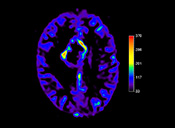

Clinical confidence in Cardiac MR